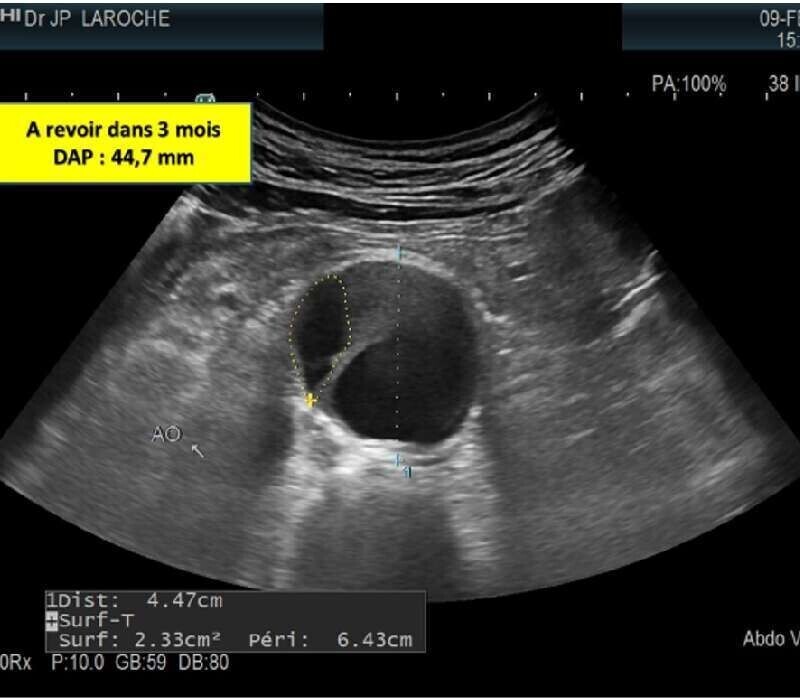

Le rythme de suivi décrit par la SFMV sera expliqué au patient.

2/ La phase préopératoire : mesure exigeante du DAP, extension sur les iliaques, identification de la mésentérique inférieure afin d'orienter ou non sa ligature en préopératoire si son DAP est de 3 mm ou plus , source d'endofuite en postopératoire.

3/ La phase postopératoire : contrôle de l'endoprothèse, mesure du DAP, examen systématique avec injection d'un produit de contraste (SONOVUE) , technique plus précise pour la détection des endofuites. Cet examen avec contraste ne sera pas répété sauf doute sur une endofuite lors de ce suivi.

4/ Suivi de l'endoprothèse : à 6 mois, puis 12 mois puis annuellement ou tous les 6 mois selon le contexte.